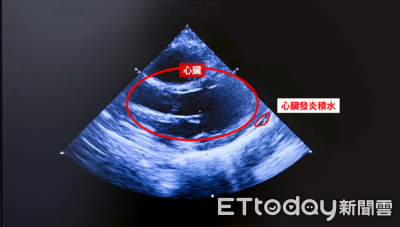

一名1歲多男童高燒合併腹瀉,體溫超過39度,原以為是腸胃炎,用藥卻未緩解不適,仍反覆發燒,並出現眼睛發紅、紅疹,及嘴唇紅腫、乾裂等症狀,經抽血與心臟超音波檢查,確診為川崎氏症,經免疫球蛋白治療後,症狀終於改善。 《詳全文...》